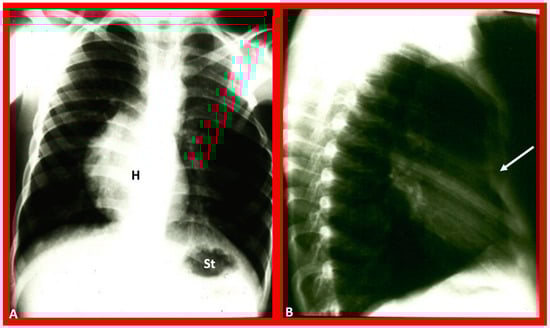

Figure 12. Chest X-rays of a five-year-old patient who was seen for evaluation since the referring physician noted a right-sided heart. Physical examination was unremarkable. (A) The heart (H) is displaced to the right, and there was no obvious pulmonary pathology. The gaseous shadow of the stomach (St) is located on the left side (normal). (B) The sternum (arrow) is showing posterior displacement, presumably causing dextroposition of the heart. Modified from reference [3].

Figure 14. Chest film in posteroanterior (A) and lateral (B) projections demonstrate a large pulmonary cyst, shown with arrows. As one can see, the heart (H) is pushed to the right, i.e., dextroposition of the heart. St, stomach bubble. Reproduced from reference [22].